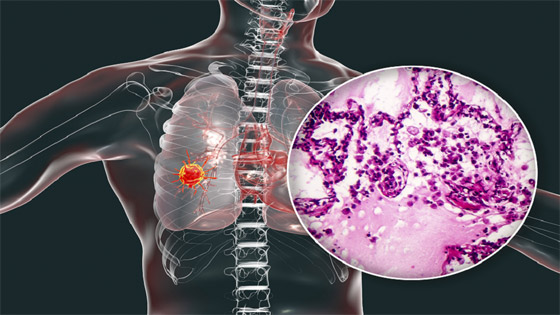

حذر أطباء متخصصون من أن تورم الوجه قد يكون علامة رئيسية على الإصابة بسرطان الرئة. يحدث تورم الوجه عندما يضغط الورم على الوريد الأجوف العلوي (SVC)، الذي يربط الرأس بالقلب، إذ يشير الأطباء إلى أن أغلب حالات انسداد الوريد الأجوف العلوي (SVCO) ناتجة عن سرطان الرئة.

ولفت الأطباء إلى أن معظم حالات انسداد الوريد الأجوف العلوي ناتجة عن سرطان الرئة أو انتشار المرض إلى الغدد الليمفاوية القريبة، بحيث تصبح منتفخة.

أعراض مالوفة

كما كشف الخبراء بالمجال أنه بالإضافة إلى تورم الوجه، قد يحصل تورم في الرقبة والذراعين وأعلى الصدر بسبب ضغط الوريد. كما تشمل الأعراض المصاحبة الأخرى ضيق التنفس أو الصداع أو تغيرات في البصر، أو ظهور أوردة زرقاء على الصدر أو الدوخة. وسرطان الرئة نادر الحدوث لدى من تقل أعمارهم عن 40 عاما، ويؤثر في الغالب على كبار السن.

ودعا أطباء إلى الإقلاع عن التدخين فورا كونه السبب الرئيسي، حيث تشير إحصائيات علمية إلى أن المدخنين يتصدرون الإصابة بهذا المرض بنسبة 70% من الإصابات.